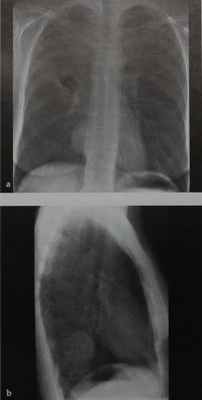

(а) На рисунке изображена опухоль оболочки периферических нервов: шаровидное мягкотканное объемное образование паравертебральной локализации.

Давление опухоли может приводить к доброкачественной эрозии костных структур и расширению межпозвонкового отверстия.

(б) Женщина 33лет, которой была выполнена КТА по поводу тромбоэмболии легочной артерии.

При сканировании в правой паравертебральной области случайно было выявлено мягкотканное объемное образование, гетерогенно накапливающее контрастное вещество.

Также было обнаружено расширение межпозвонкового отверстия на уровне позвонка Th8 и распространение опухоли в спинномозговой канал. При биопсии под ультразвуковым контролем был подтвержден диагноз шванномы. (а) При рентгенографии органов грудной клетки в боковой проекции в паравертебральной области определяется объемное образование, характеризующееся симптомом неполного контура вследствие внелегочной локализации.

Картина позволяет заподозрить опухоль оболочки периферических нервов: для исключения распространения опухоли в спинномозговой канал была назначена МРТ.

(б) При МРТ на совмещенных Т1 (вверху) и Т2 (внизу) взвешенных изображениях визуализируется овоидноеобъемное образование гомогенной структуры, гипоинтенсивное на Т1ВИ и гиперинтенсивное на Т2ВИ.

Биопсия под контролем КТ позволила подтвердить диагноз шванномы.